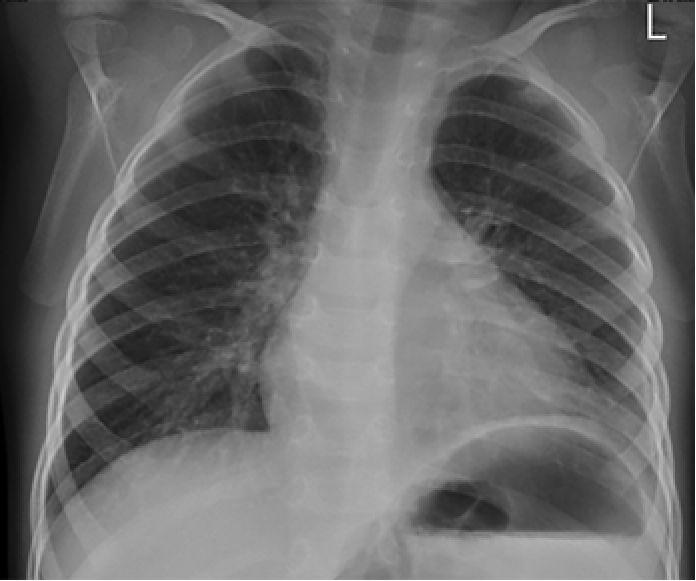

На третий день болезни при рентгенографии органов грудной клетки выявлено снижение прозрачности левого легочного поля в базальном отделе (инфильтративные изменения), а также небольшое количество выпота в левой плевральной полости с затенением реберно-диафрагмального синуса (рис. 1).

Рис. 1. Рентгенограмма органов грудной клетки в прямой проекции мальчика Б. на третий день болезни. Левосторонняя нижнедолевая пневмония, левосторонний гидроторакс минимального объема